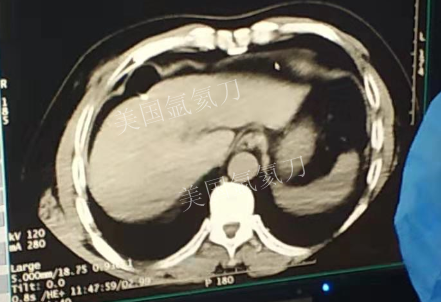

59岁男性肝部氩氦刀手术治疗